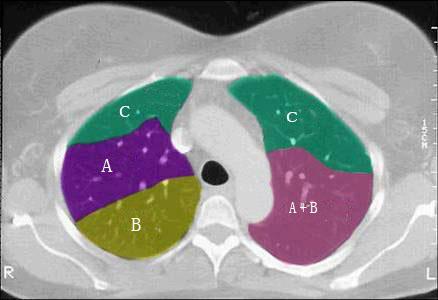

问题 结合肺段模式肺动脉干与右肺动脉层面肺动脉干与右肺动脉层面、心室层面、主动脉弓层面、 左右心房层面(如图),选出左肺上叶的组成 ( )

选项 A.A+B B.A+B+C C.A+B+C+D D.A+B+C+D+E E.A+B+C+D+E+F

答案 D